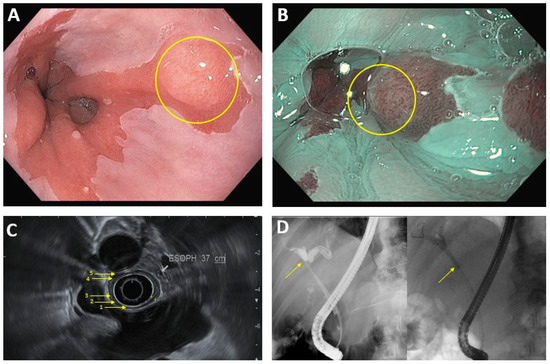

3.1. Luminal Upper GI Cancer

3.2. Pancreaticobiliary Cancer

4. Treatment of Cancer